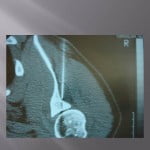

Biopsie sous guidage scanner